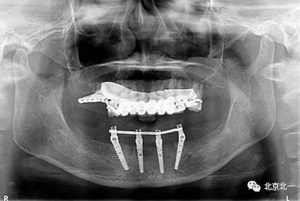

圖十五:術(shù)后即刻拍X片

圖十六:術(shù)后三個(gè)月永久修復(fù)取模,夾板固定。

圖二十一:半年后復(fù)查X片

圖二十二:2015年到2016年復(fù)查時(shí)X片 ,有圖有真相